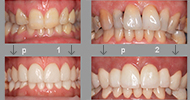

Dentalna estetika uključuje sve zahvate kojima se poboljšava pacijentov osmijeh. Često se koriste ljuskice i krunice.